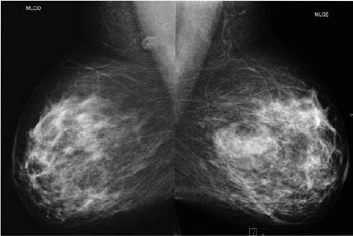

Paciente de 40 anos realizou esta mamografia para rastreio, sendo assintomática. A ultrassonografia realizada em outro serviço, 6 meses antes da mamografia, demonstrou pequeno nódulo hipoecoico de 1,5 cm no QSE da mama direita e nenhuma lesão na mama esquerda. Assinale a alternativa correspondente à hipótese diagnóstica da imagem nodular da mama esquerda observada na mamografia.

Assinale a alternativa que apresenta corretamente o que observa-se na análise das imagens da mamografia.

Uma paciente de 46 anos realizou esta mamografia.

Assinale a alternativa que contém a descrição e a classificação BIRADS correspondente.